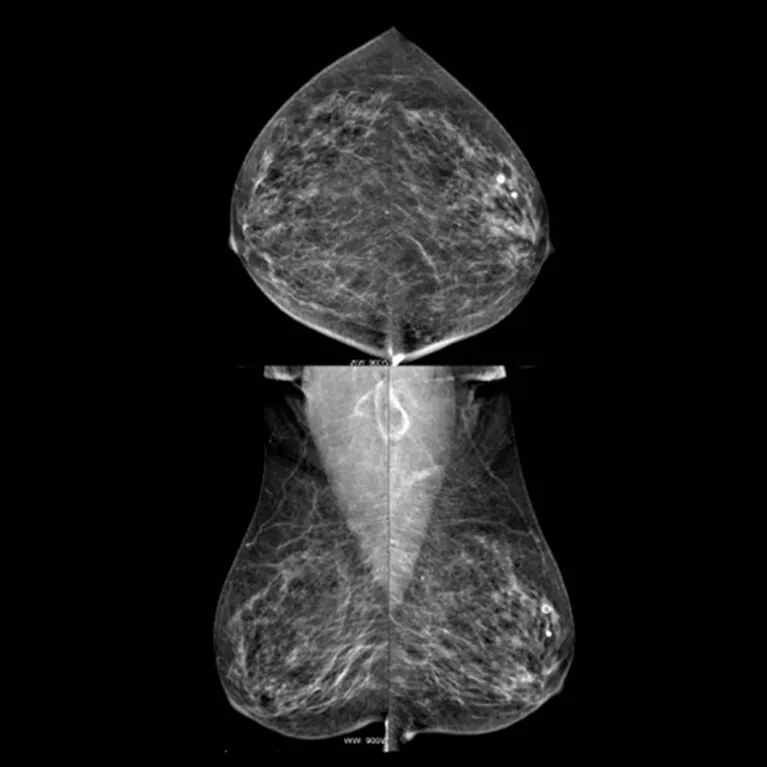

MG

MG—全称是乳腺X线摄影,也是老百姓常说的“钼靶”,是利用X线给乳腺拍照片。它的特点是“”、“对称”。MG拍出来的照片也是重叠的、拍“扁”的照片;又因为乳腺是成对的器官,每一侧乳腺拍摄两张标准体位,所以,通常一张MG检查的胶片一共有会4张照片,左右对称排列。